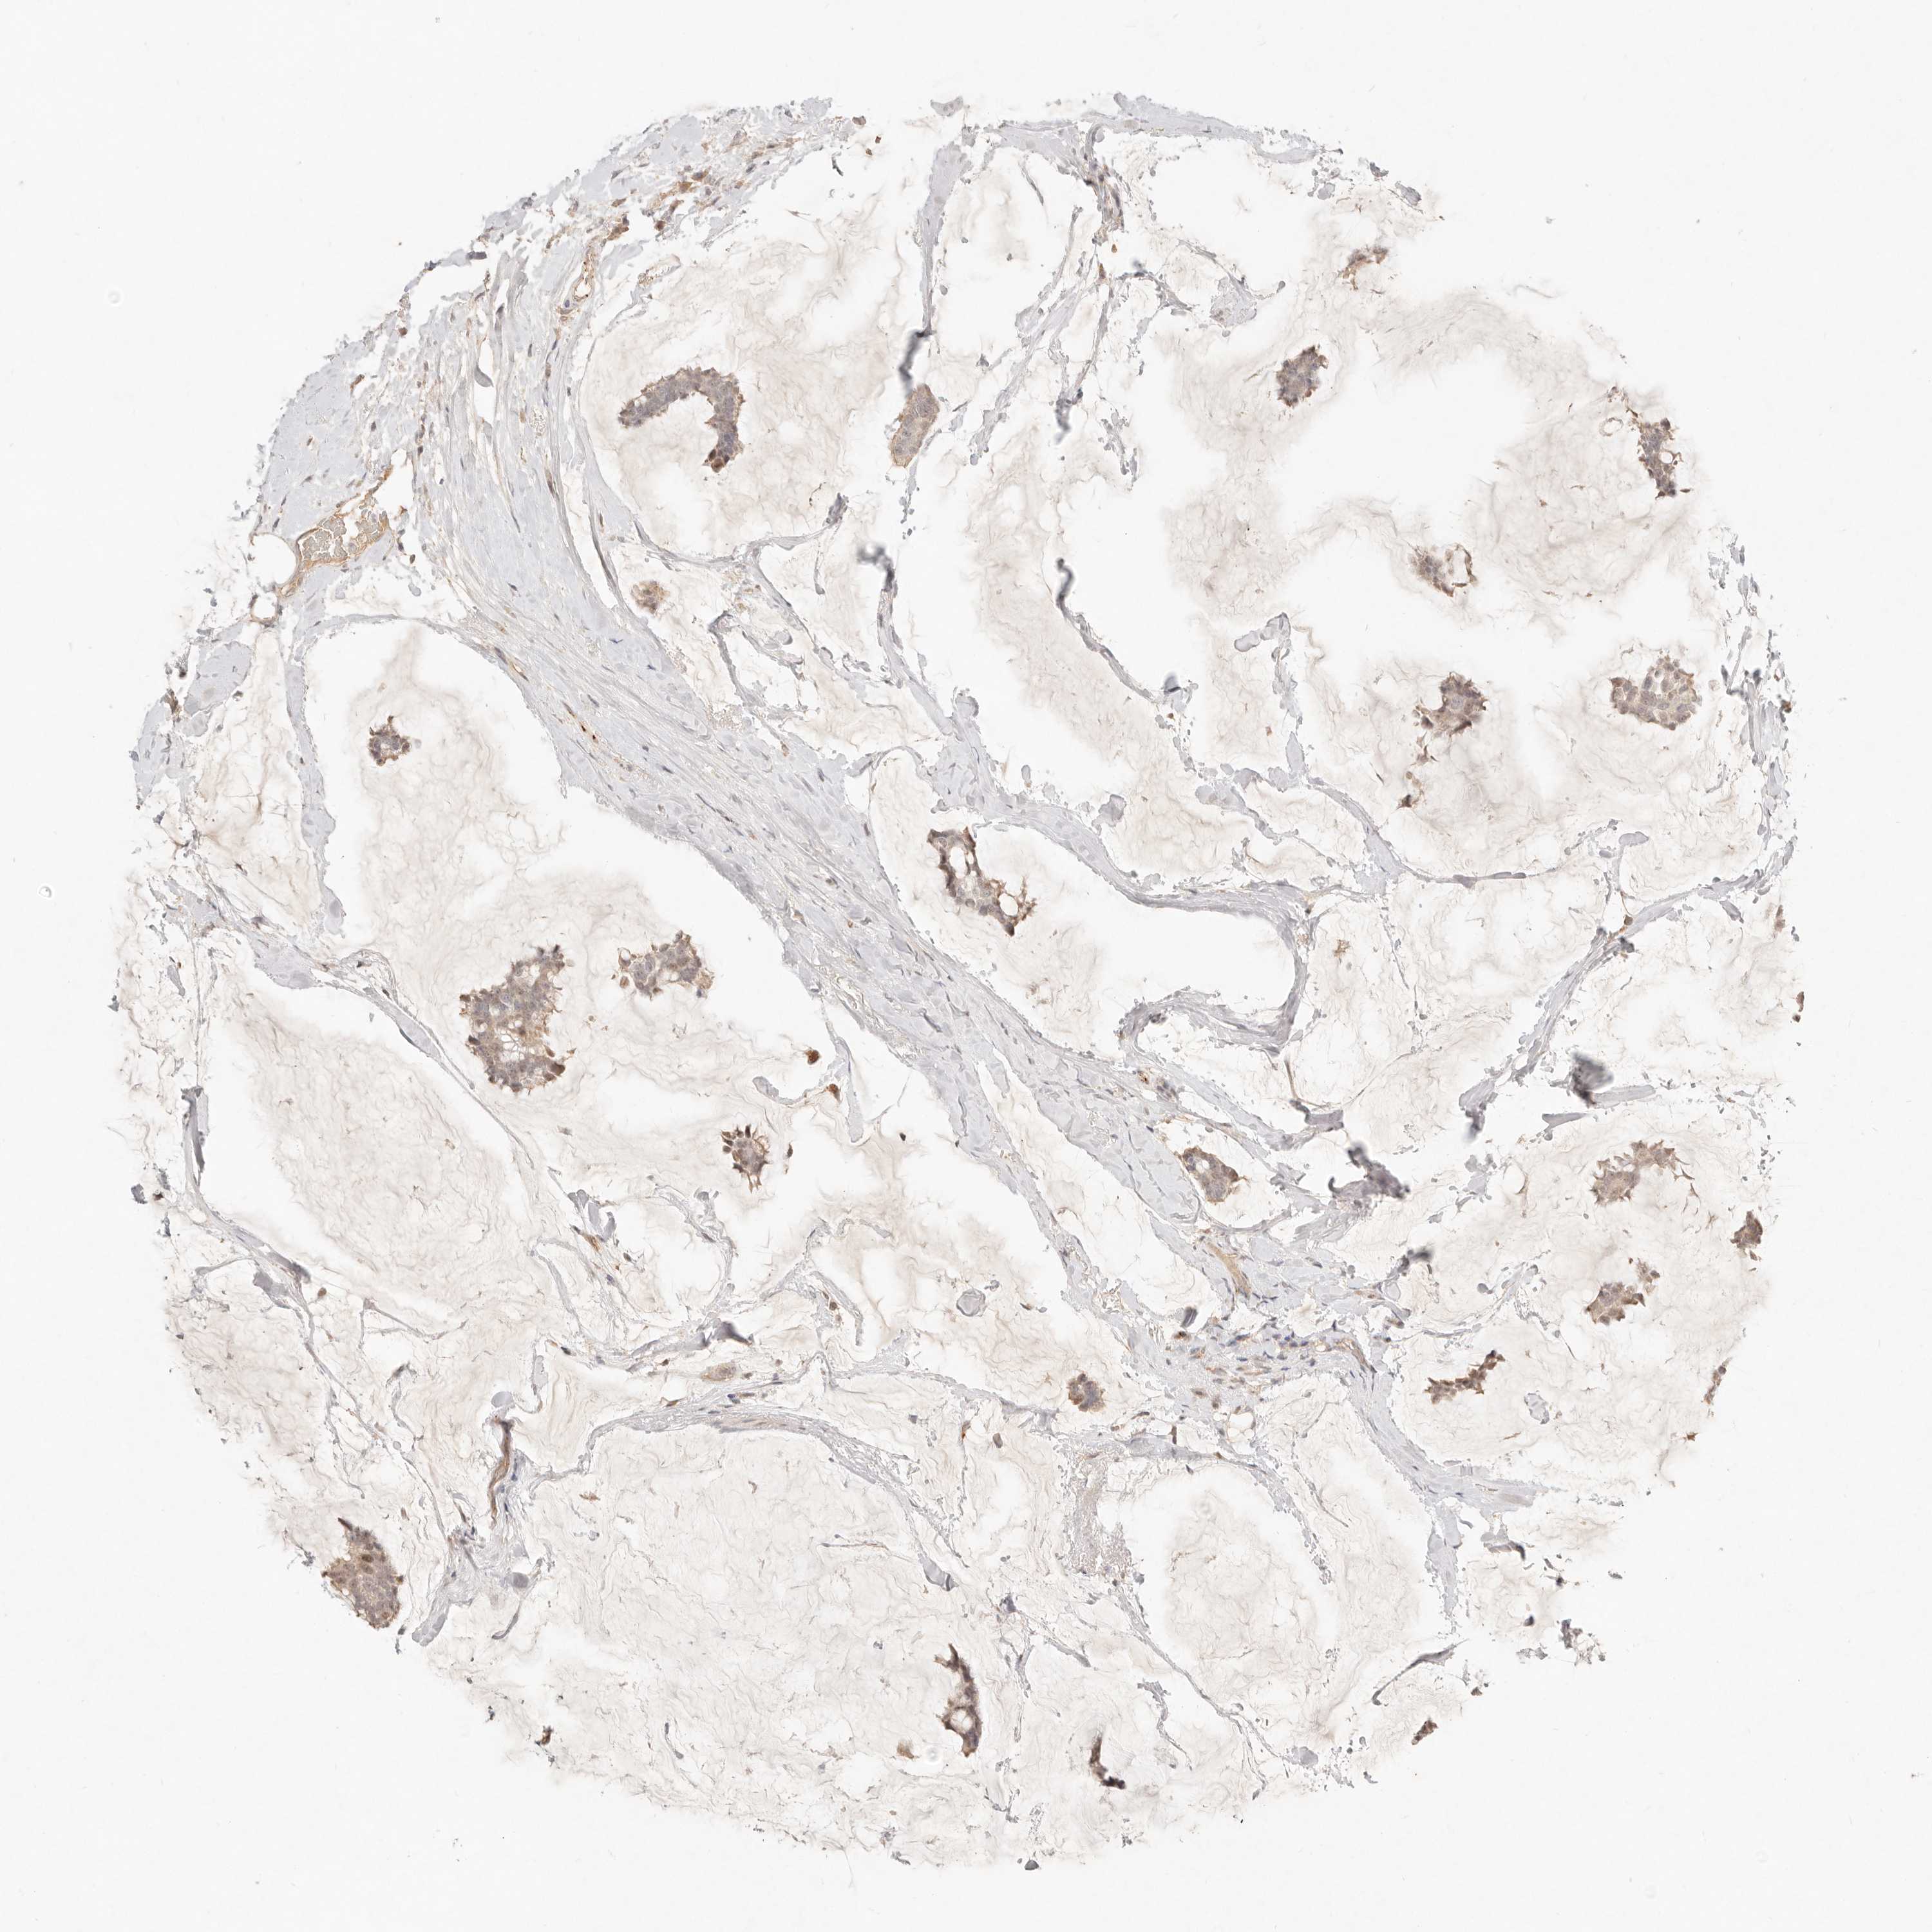

CANCER BREAST CANCER Show tissue menu

BRCA TCGA BRCA VALIDATION PROTEIN EXPRESSION